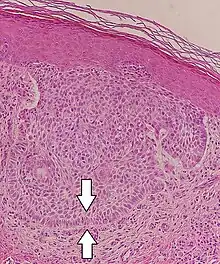

Nodular basal-cell carcinoma

Nodular basal-cell carcinoma (also known as "classic basal-cell carcinoma") accounts for 50% of all BCC.[29] It most commonly occurs on the sun-exposed areas of the head and neck.[30]: 748 [31]: 646 Histopathology shows aggregates of basaloid cells with well-defined borders, showing a peripheral palisading of cells and one or more typical clefts.[29] Such clefts are caused by shrinkage of mucin during tissue fixation and staining.[32] Central necrosis with eosinophilic, granular features may be also present, as well as mucin. The heavy aggregates of mucin determine a cystic structure. Calcification may be also present, especially in long-standing lesions.[29] Mitotic activity is usually not so evident, but a high mitotic rate may be present in more aggressive lesions.[29] Adenoidal BCC can be classified as a variant of NBCC, characterized by basaloid cells with a reticulated configuration extending into the dermis.[29]

Cleft.